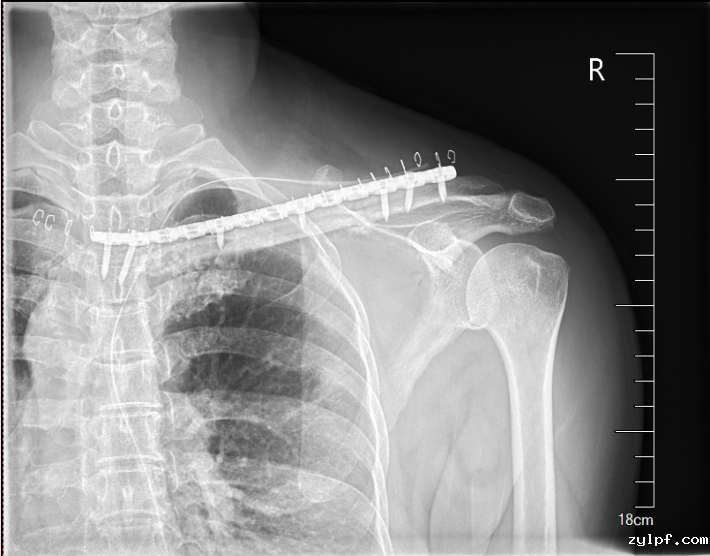

完善术前评估及准备后,王伟东副主任团队为患者实施了右锁骨胸骨端继发型软骨肉瘤扩大切除术+自体腓骨移植重建术。术中见肿物与颈总动脉、头臂静脉相邻紧密,王伟东副主任凭借扎实的手术技术,完整将肿瘤和临近大血管分离,完整切除肿瘤。目前患者伤口恢复良好,已逐步开始康复锻炼,肩关节活动无障碍。

图片 4.png

图片 5.png

图片 6.png